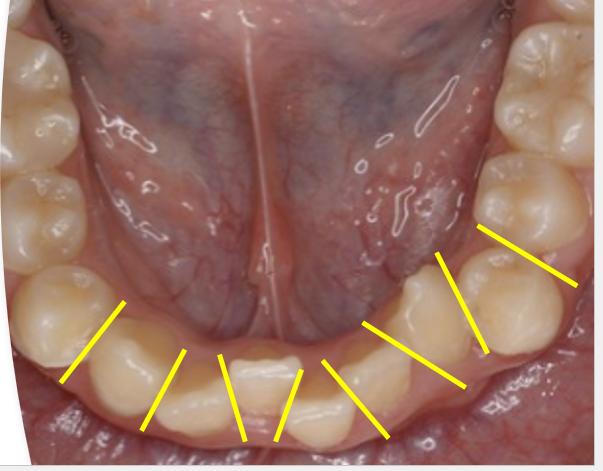

いきなり1枚目でIPRをすると…

①コンタクトポイントでない部分を削るリスク。

②歯が、ギザギザになってしまうかも…

③そもそも、IPR処置が行いにくい状況…

このようになってしまいます。